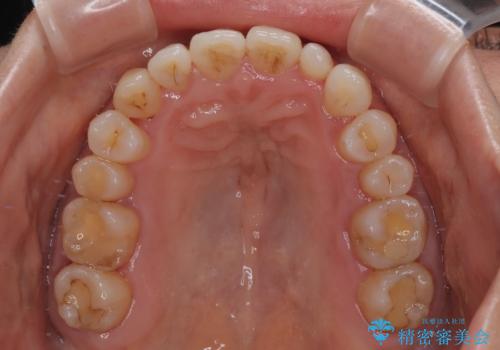

骨格的なズレを歯列矯正でカバー ワイヤー装置での非抜歯矯正

予想通り左側の咬み合わせの調整に苦労をしましたが、最終的には違和感のない咬み合わせを達成することができました。